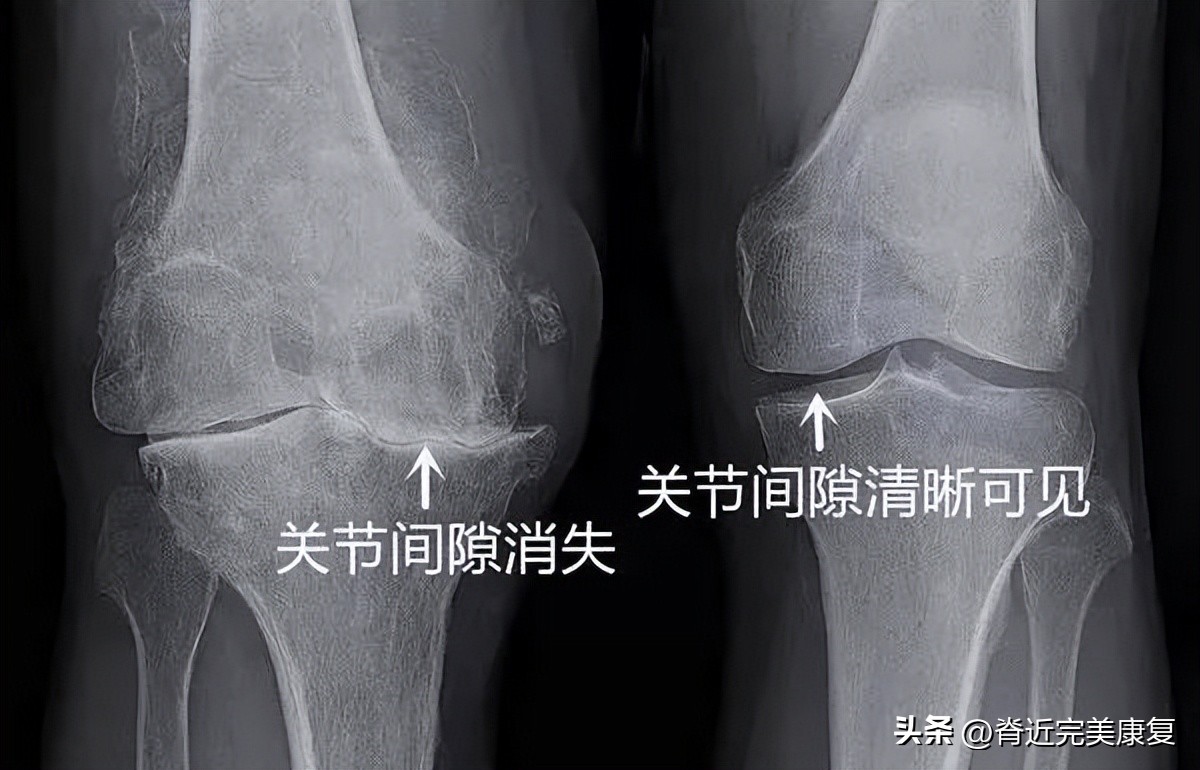

骨关节炎是由覆盖骨头末端的软骨磨损引起的。柔软又坚韧的软骨有助于关节灵活活动,但随着年龄的增加,软骨的表面发生不可逆的受损,严重时软骨下的骨头直接相互摩擦。

这种摩擦会导致关节疼痛、肿胀、变形,甚至关节的边缘还会长出骨刺。